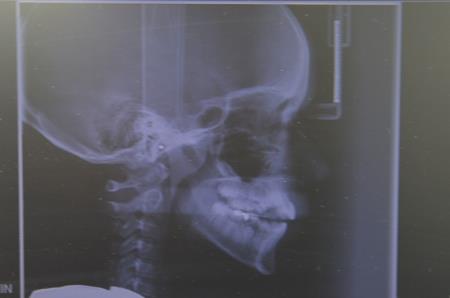

S septembrom lahko »naša« ortodontka končno nudi specialistično zdravljenje zobnih in čeljustnih nepravilnosti na napotnico za otroke in mladostnike tudi doma v Bovcu, v koncesijski zobni ordinaciji Dentalnega centra dr. Lah Kravanja.

Ortodontka Sanda Lah Kravanja je navdušena spomnila prvih pobud in povedala: »Zelo sem vesela, da nam je po dolgih letih prizadevanj uspelo doseči nov cilj za otroke, starše in domači kraj. Ob lanskem praznovanju 20 letnice delovanja Dentalnega centra dr. Lah Kravanja sem tudi javno izrazila pobudo Ortodonta za otroke na napotnico tudi v Bovec, vsaj za en dan v tednu in za nami je res intenzivno leto angažiranja na vseh nivojih. Nisem še pozabila dolga tri leta vsakodnevne vožnje iz Bovca v Ljubljano in nazaj na specializacijo v UKC Ljubljana, ki sem jo zaključila že leta 2011. Od takrat sem lahko v Bovcu zdravila le samoplačnike, končno pa bom lahko svoje znanje ponudila na napotnico; čaka nas veliko novega, a lepega dela z otroki. Ordinacija bo delovala ob petkih, tako da bo ugodno tudi za tiste, ki se zaradi šolanja le za vikend vrnejo domov. Vsem skupaj bo prihranjenih veliko poti. Za samo delo je bila obnovljena že obstoječa koncesijska ordinacija, saj potrebujemo dodatni prostor za materiale, instrumentarij, modeloteko in zdravstveno dokumentacijo. Trenutno poteka usklajevanje obstoječih čakalnih vrst, vendar že sprejemamo tudi nove vpise. Pričakujemo predvsem napotitve v Zgornjem Posočju, otroke z bovškega, kobariškega in tolminskega območja. Otroci potrebujejo napotnico izdano od zobozdravnika, saj gre za napotitev na specialistični nivo. Napotnica se lahko izda takoj, ko je prepoznana potreba po ortodontskem zdravljenju. Za nadaljnje postopke in vodenje čakalnih knjig pa smo dolžni spoštovati predpise in pravila ZZZS, ki je plačnik specialistične obravnave. Upam, da bo tudi sistem E-zdravje, v katerega je vpet ZD Tolmin, dobro deloval tudi na najbolj oddaljenem delovišču v Posočju. Zelo se veselim petkov z otroki v domačem kraju.«